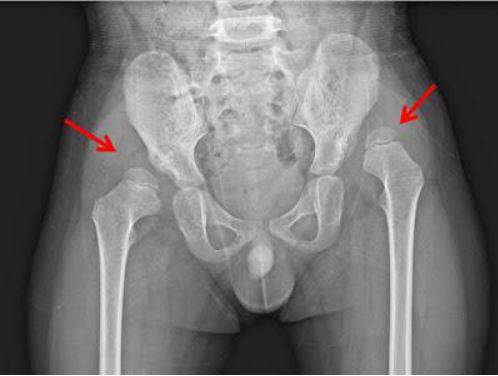

包巾包覆過緊確實可能導致嬰兒髖關節發育不良。這是因為過緊的包巾會限制寶寶雙腿的自然活動,使髖關節長時間處於內收和伸直的狀態,無法保持正常的外展(打開)和彎曲姿勢,進而影響髖關節的正常發育。

- 傳統將寶寶雙腿緊密綁在一起的包巾包法,是髖關節發育不良的高風險因素之一。

- 正確的包覆方式應讓寶寶雙腿呈現「青蛙腿」或M型腿姿勢,即雙腿自然張開、彎曲,類似騎馬姿勢,這樣能促進股骨頭與髖臼的良好包覆,保護髖關節健康。

- 若包巾包覆過緊,可能導致髖關節發育不良,嚴重時甚至會影響寶寶一生的行走功能。